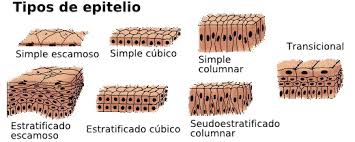

TEJIDO EPITELIAL:

El epitelio de la mucosa oral es de tipo plano o escamoso pluriestratificado.

1.- Epitelio plano pluriestratificado queratinizado: